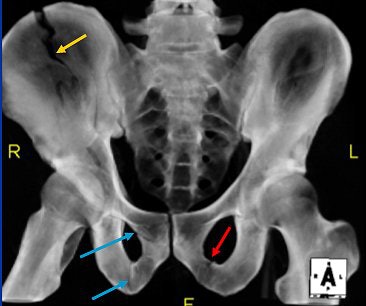

![]() |

| Translucent 3D volume-rendered CT of AP pelvis. Fracture involving right iliac wing (yellow) and right obturator ring (blue arrows), which in combination relate to anterior column fracture. This is more easily seen on reformatted 3D image reconstructed from trauma CT. Additionally, a left inferior pubic rami fracture is seen (red arrow). |